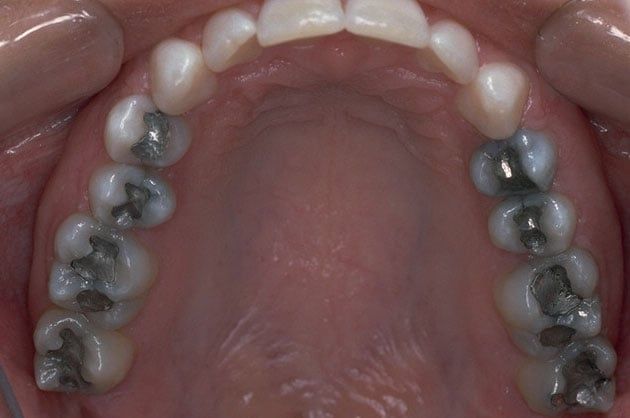

Tooth-colored fillings, white fillings and composite resin fillings are all names for the high-strength, natural-looking fillings that can be placed today instead of silver or gold (also known as amalgam fillings). No matter what the name, Myers Pediatric Dentistry & Orthodontics will know just what you're talking about when referring to this natural-looking filling.

Composite fillings are today's modern filling choice. They are made to match your tooth's natural color to make them virtually invisible to notice and are placed onto the tooth by bonding the filling material to the tooth so they do not have the unlikely chance of falling off. Many patients choose to replace their old silver and gold fillings with composite fillings.

White fillings are made from a high-strength composite resin that can be easily color-matched to your natural tooth making it nearly invisible to you and anyone else. Unlike silver and gold fillings, composite tooth-colored fillings actually bond to the tooth which means they support the surrounding tooth structure, which helps to prevent breakage and insulate the tooth from excessive temperature changes. You are much less likely to have a composite filling fall out which is a common issue with metal fillings.